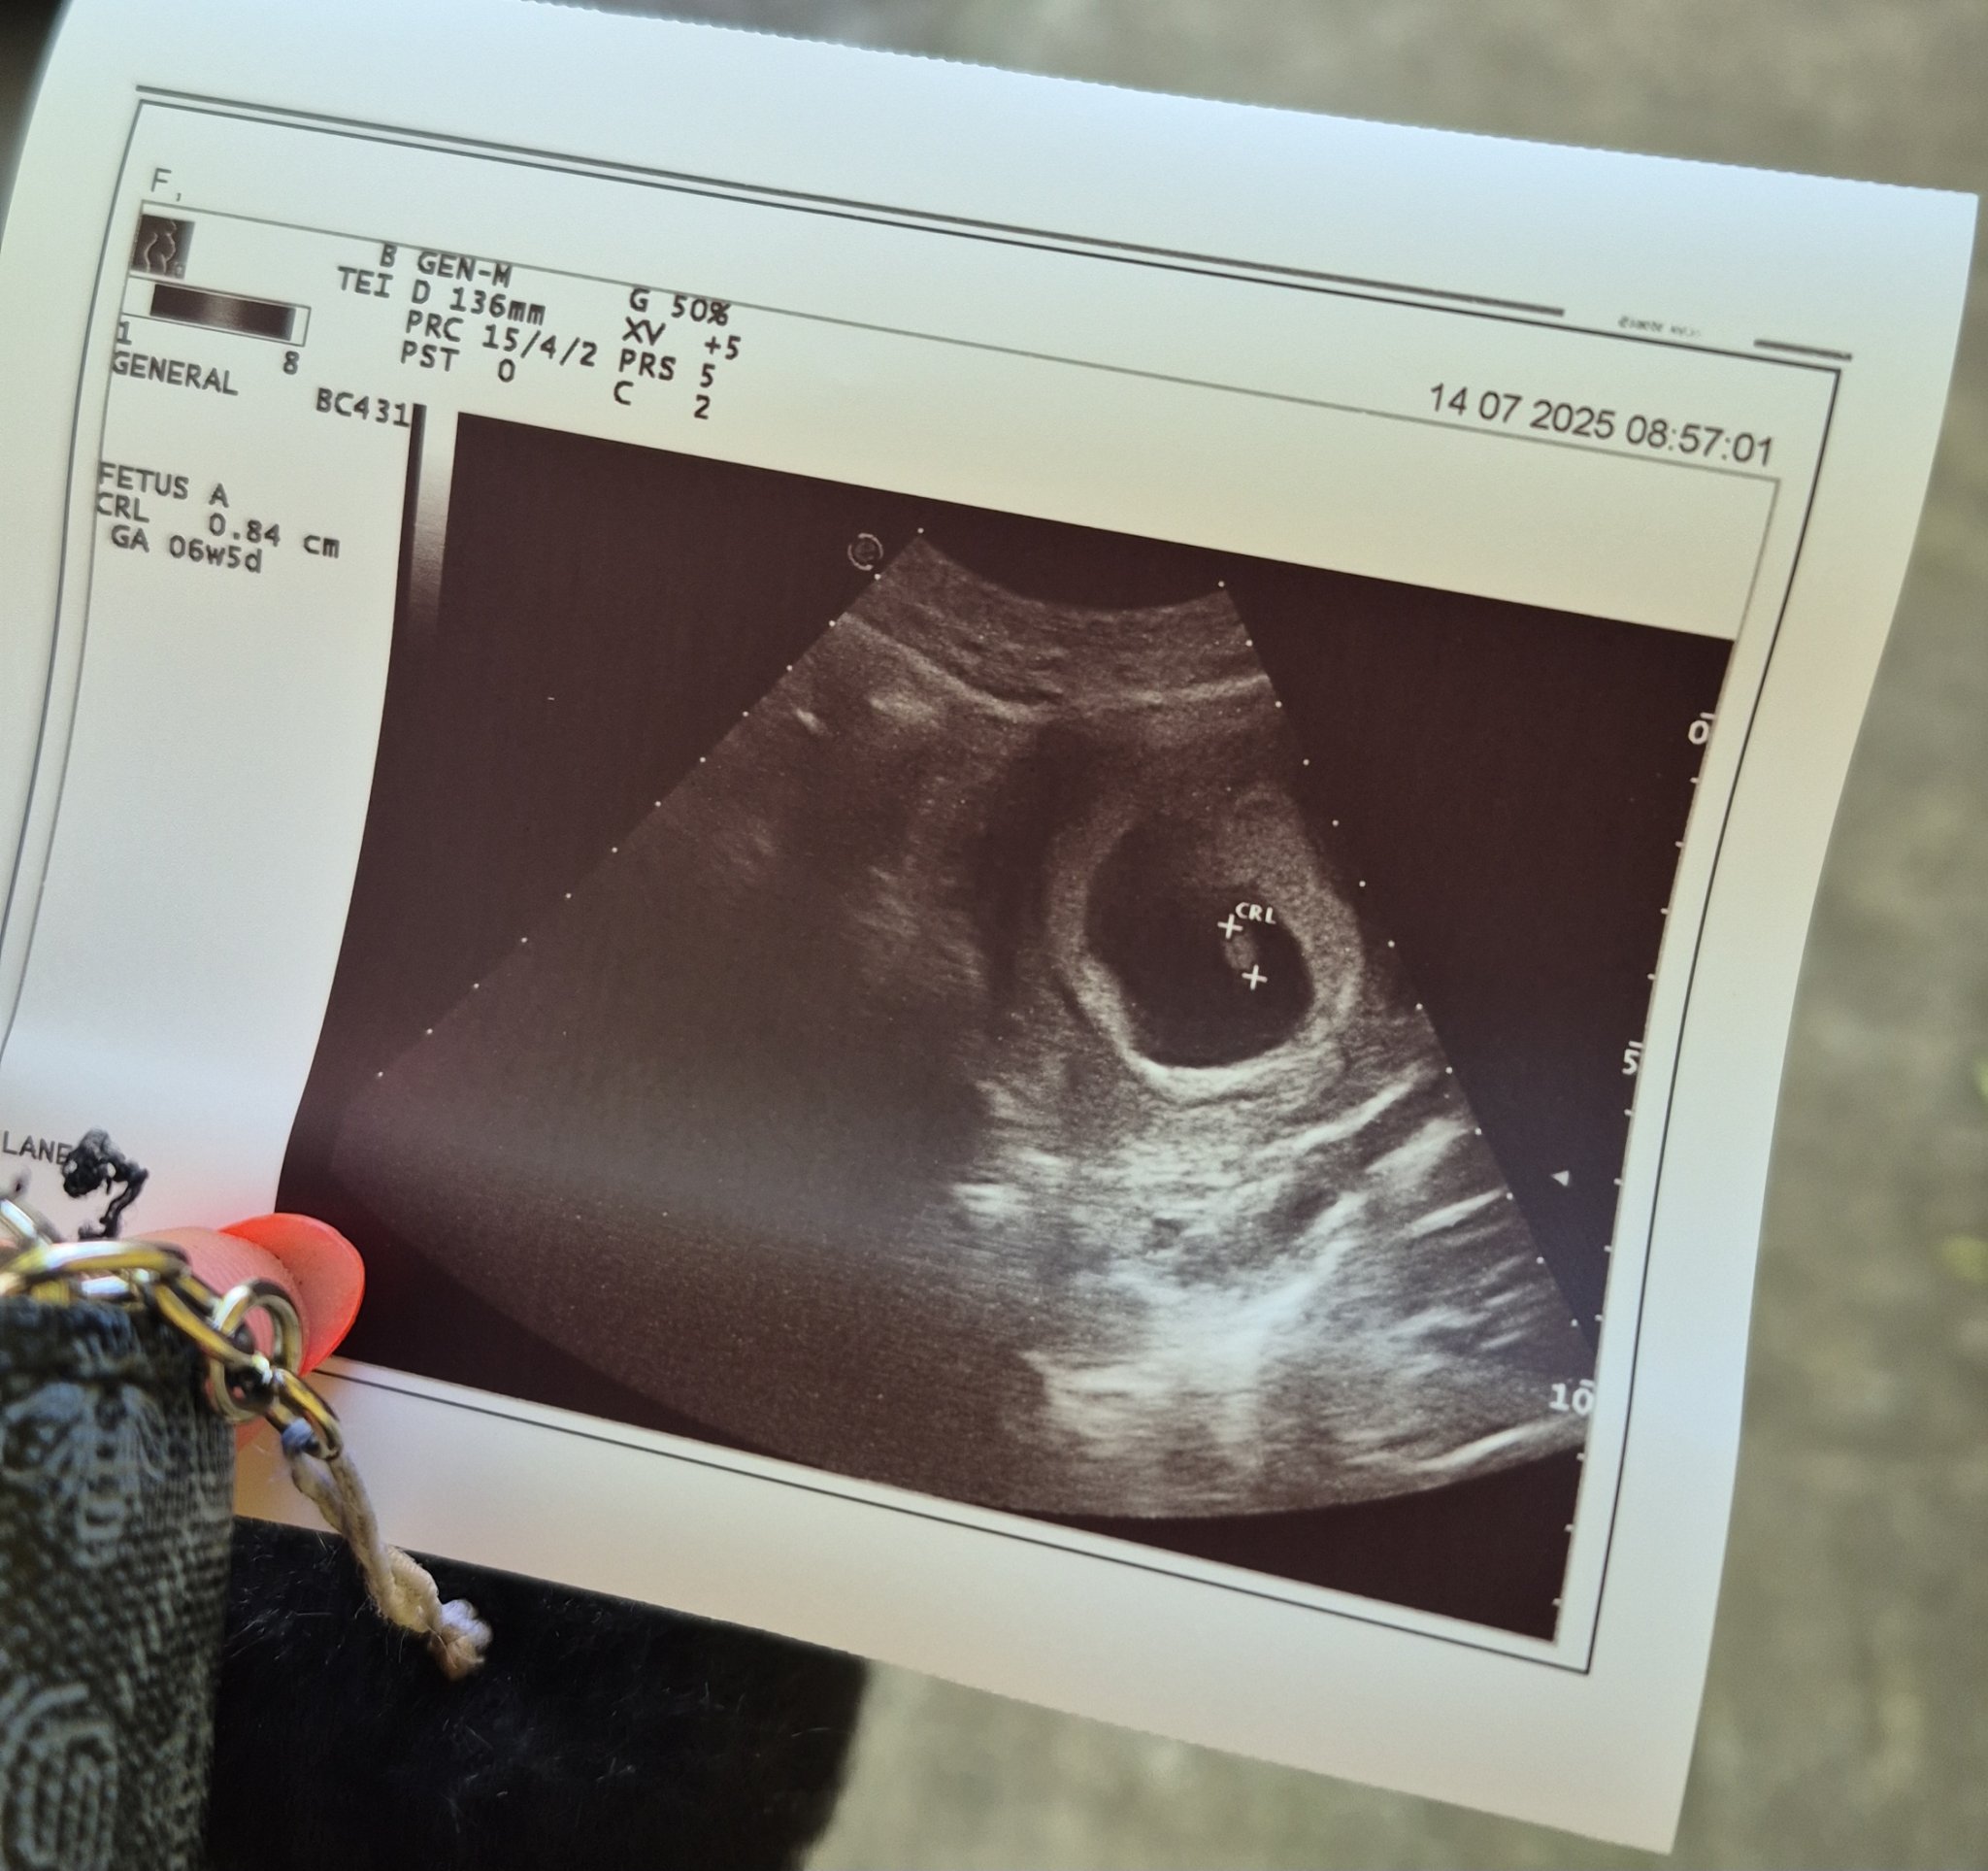

Здравейте, отново съм аз. Имам чувството, че всеки ден мога да ви пиша, тъй като много много се вълнувам. Тази сутрин отидох на преглед понеже много ме болеше корема и кръста, всичко е наред така ми казаха, болката била понеже съм вдигала нещо по-тежко и ми казаха да не вдигам нещо повече и да внимавам като се навеждам. Не ми казаха обаче в коя седмица съм, общо взето нищо не ми казаха. На първия преглед ми казаха, че съм в 5та г.с., по мои изчесления от датата на последния ми цикъл съм в 8 г.с + 1ден. Дадоха ми снимка но не разбирам на нея нещо дали пише

Stubborn, не ти ли казаха нищо за ехографията, какво се вижда…Почти съм сигурна, че това ти е ембриончето, 0.84 см.

Даа, казаха ми, че е ембрион, но нищо повече. Нито в коя седмица месец съм нищо. Само ми казаха да не вдигам тежко да внимавам и това беше..

То пише 6 седмици и 5 дена